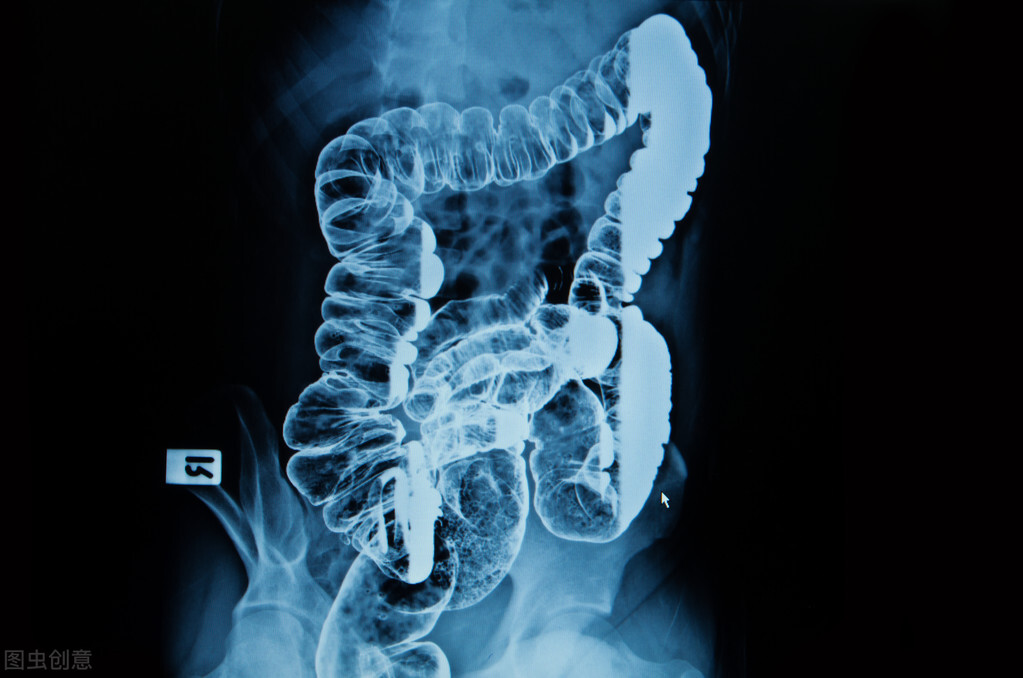

1 灌肠种类 1.1 保留灌肠法:一般用小剂量的灌肠液保留在肠道以治疗某些疾病,如中药制剂治疗肠道疾病、肾功衰竭等;10%氯化钾溶液补充体内钾离子,调节低血钾症状。医用软皂液、开塞露、石蜡油等润滑肠道解决严重便秘,还有使用镇静作用的栓剂,有解热、镇痛、镇静的作用。 1.2 手工清洁灌肠法:普通手术前肠道准备、肠道镜检查及肠道手术等,均需要清洁灌肠。根据患者病情需要多次灌肠,目的是使肠道清洁,避免术中对肠道损伤或因肠内容物多、产气多而影响术野。某些清洁灌肠是相对的,而对于肠道手术,患者的清洁灌肠则是绝对的,只靠1~2次灌肠不一定达到理想效果 ,还要在术前进行肠道准备,如肠道手术患者一周前开始进半流食或全流食,术前1~3d口服肠道准备药物(促进排便),防止粪块或肠壁黏液影响手术的顺利进行,否则易造成腹腔感染,术后愈合不好,同时对于体质本身较差的患者也存在许多风险。 1.3 采用结肠灌注机灌肠法:采用结肠灌注机能减少患者体力的消耗,不用反复上厕所排便,灌出的肠内容物直接由**管进入下水道,更适合于老年体弱、活动受限的患者。采用灌肠液由生理盐水、清水、医用软皂水等。我院引进结肠灌注机两年多,取得较好灌肠效果。

2 灌肠时肛管插入放入长度及体征 2.1 保留灌肠肛管插入的长度与**:协助患者左侧卧位,双腿屈曲,嘱患者深呼吸,减轻腹部压力,缓慢插入肛管14~17cm时,肠内保留灌肠液体较多,排便敏感度较弱;保留药液时间较长,使灌肠液保留得更充分,起到疗效作用。 2.2 手工清洁灌肠肛管插入的长度与**:肠道的清洁主要通过**插入肛管,灌入大量洗肠液来实现。插入长度如不适宜,必将影响清洁洗肠的质量。**距直肠起始端长度为15~19cm,而其中外科解剖肛管长度平均约为3~4cm,直肠长度为12~15cm,肛管的顶孔距侧孔距离为1.0cm,而在直肠的7~9cm为排便反射最敏感的地方(直肠手术也常保留此部位,以保持正常的排便功能),当清洁洗肠将肛管插入7~10cm时,肛管尖端正好大直肠排便反射最为敏感的部位,所以当有水流**及直肠内容物增加**肠壁时,患者出现腹胀、腹痛,有排便感觉,致患者不能接受洗肠液继续流入肠道,以致清洁肠道不彻底,清洁洗肠的总时间延长(需反复清洁洗肠)。当插入肛管14~17cm时,肛管尖部所达到部位正好避开了直肠排便反射最敏感的部位,因而可使进入肠道中灌洗液的量更多,洗肠液可大量进入乙状结肠,而不至于过早出现患者排便现象,同时也使清洁洗肠的总时间缩短,清洁洗肠的效果更满意。

患者**根据其病情不同及个体差异也不同。采取左侧卧位较多,当直肠内粪便排除后,可以采取再仰卧位—右侧卧位—左侧卧位,也可以适当变换**,使灌肠液充分溶于肠腔内。特殊患者因身体情况采取坐位,护士操作难度相当大,为了人性化的服务,操作者要克服许多困难,长时间弯下腰为患者插入**管,对护士的健康造成损害(腰椎不健康者不易操作),且灌肠时间超过1h后,灌肠效果不佳。 2.3 结肠灌注机灌肠肛管插入的肠道与**:肛管插入的肠道根据患者病情需要选择,一般情况与手术操作长度相同,一位经验丰富的操作者会选择长短不一的长度交替进行,当**管插入**时,患者会有不适感,应嘱患者深呼吸,用纱布块、润滑油充分润滑肛周,当灌肠液体循环系统打开后,缓慢插入肛管,由浅入深进入肠腔,当肛管插入7~10cm时,排便感觉敏感;插入14~17cm时,排出的粪便较多,开始多为成型便,随着排出粪便量减少时,感官可继续延伸,最长可达到60cm,灌肠液可达到降结肠顶部,液体亦可进入横结肠,因为灌肠机有一定的压力推液体进入肠腔。